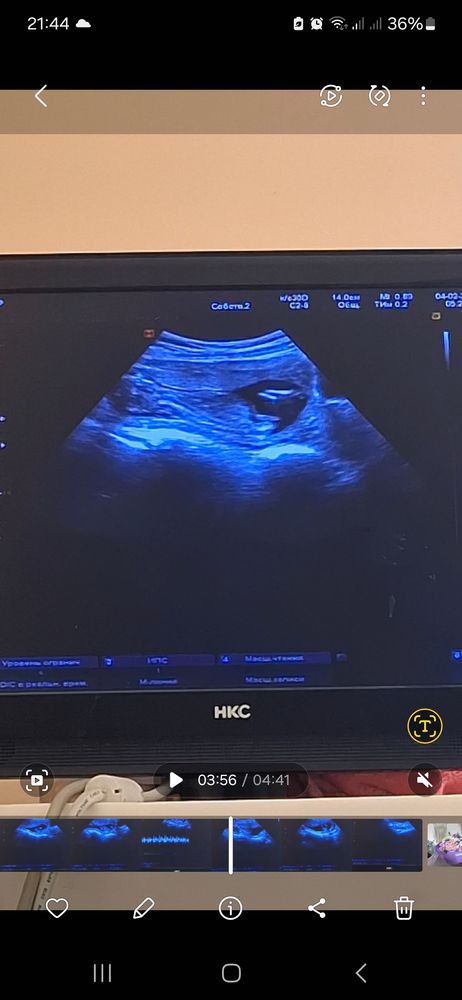

Решила узнать пол, первый Врач смотрел сказал похож на мальчишку что то между ног есть,я лишь увидела половой бугорок и спросила разве с мальчиками он не должен на 30 градусов быть выше ,он ответил что это не 12 неделя чтобы определять по положению полового бугорка, фото прикреплю.

Пошла к другому, тот же сказал что ничего нету и похожа больше на девочку, Если кто разбирается? Девочка или мальчик это?

Ну похожа на девочку😅 если я правильно вижу штучку по середине.

У мальчиков вроде вверх торчит а у девочек под наклоном

У меня почти на таком же сроке как у вас, этот половой бугорок уже четко вверх торчал, хоть на 12 и не так, больше на девочковый смахивал на 1 скр. Исходя из этого, думаю, что это девочка 🩷

С дочерью была в 15+3 на УЗИ, там прямо четко уже девочка была, без вариантов и половых бугорков) Тут больше похоже на мальчика.